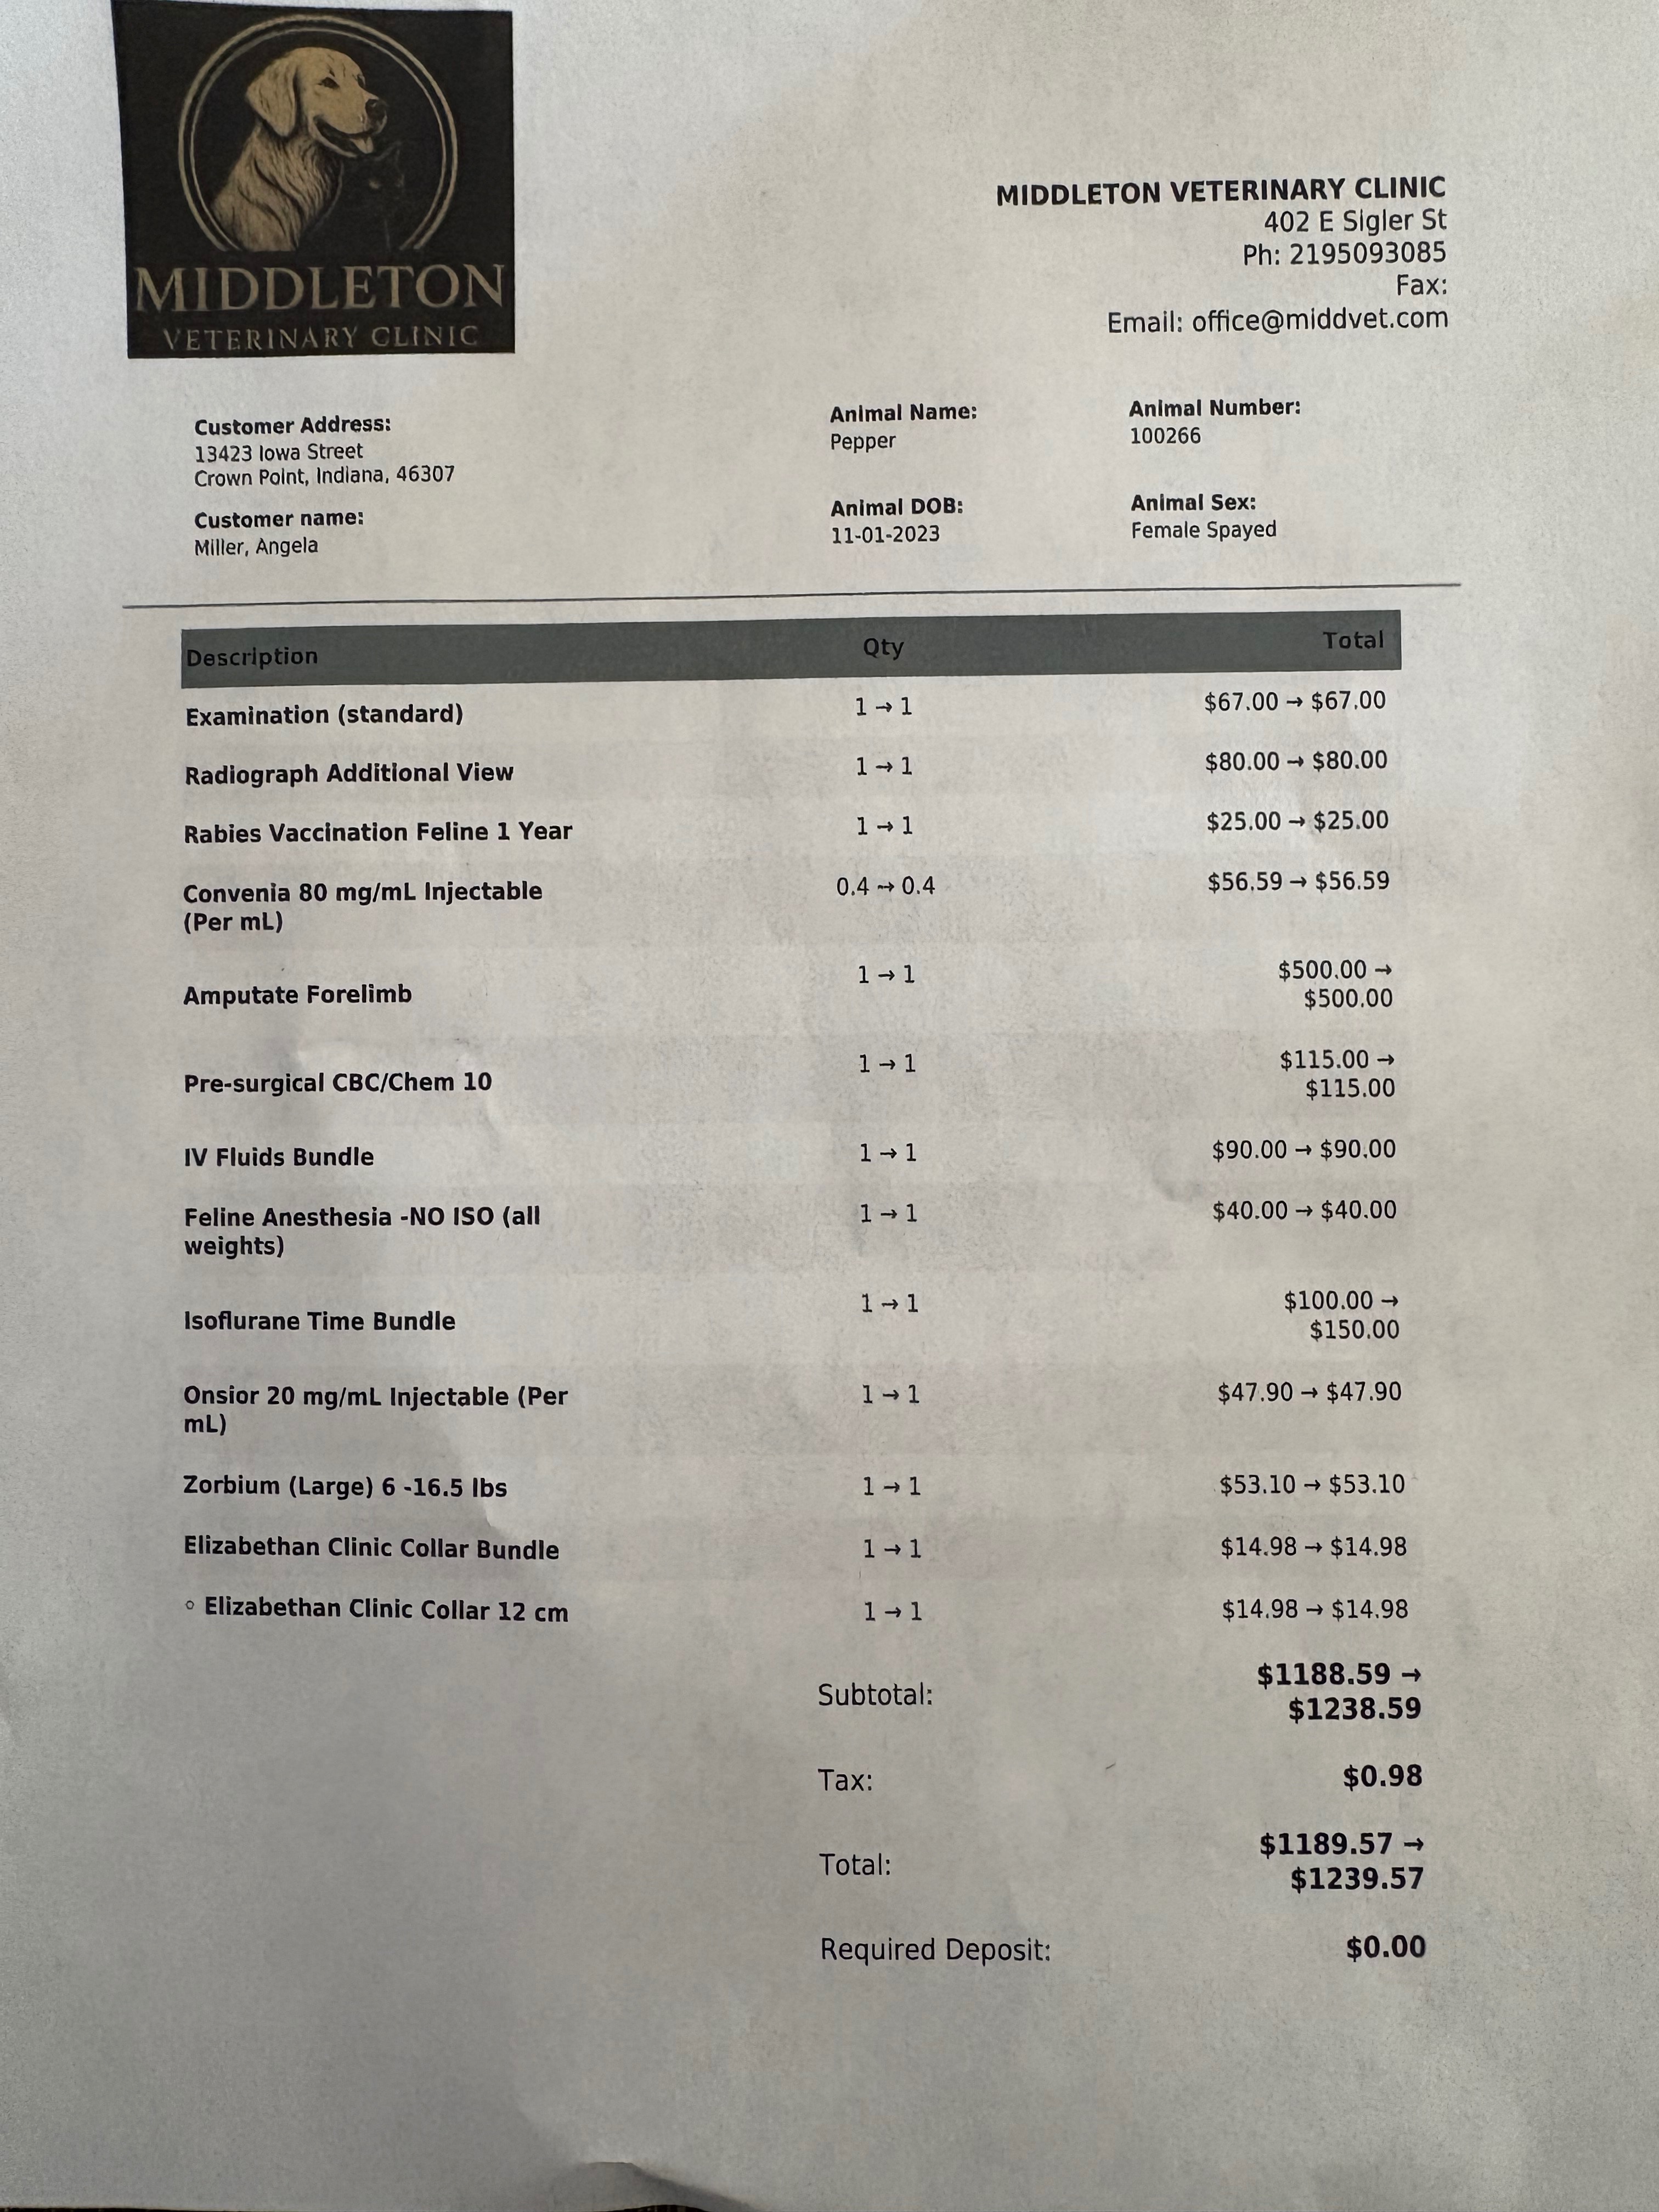

Instead of putting her down, we chose surgery. Pepper’s amputation surgery is estimated to cost $1,239.57. This is a huge expense for our family right now.